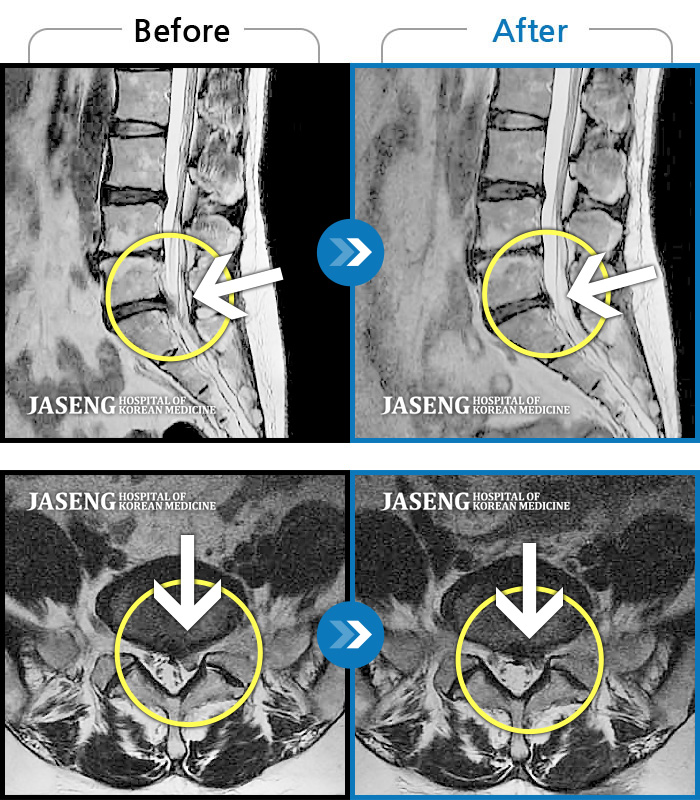

허리디스크

잠실 · 한상욱 원장

허리가 많이 아프고 왼쪽 다리가 저려 움직이기가 힘들다.

촬영시기

2022.01.19 ~ 2022.11.14

2022.12.02